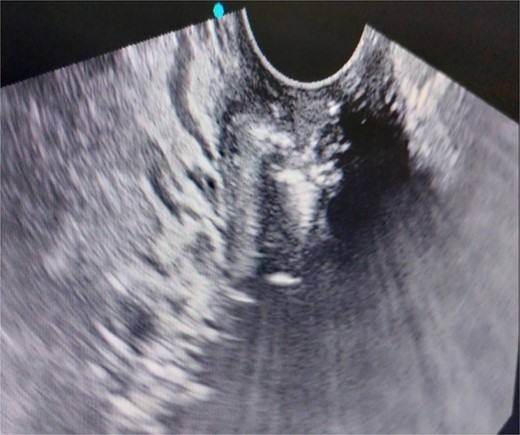

A 26-year-old nulliparous lady from a rural area was referred to emergency from a primary health care centre with a failed attempt to remove an impacted uterine foreign body. On per speculum examination, an impacted hard pipe-like structure was protruding from the cervix. The patient gave a history of foreign body insertion 9 years back, however, failed to provide a detailed account of the mode of insertion or history of sexual assault. She went to seek medical care only after developing profuse foul-smelling discharge and chronic pelvic pain. Removal was attempted under local anaesthesia but failed. Transvaginal scan showed a bulky uterus with an apparently normal endometrial thickness and echotexture; however, the cervical canal was distended with an echogenic area and areas of calcification (Figs 1 and 2). She was taken up for removal of the foreign body under general anaesthesia. As a hard pipe-like structure was already protruding, removal was tried by grasping it with a Kocher’s forceps. After multiple attempts part of the foreign body was removed. Hysteroscopy showed that the lower endocervical canal was clear and a ring-like structure occupied the upper endocervical canal. Removal under direct vision using a hysteroscopic grasper was attempted but failed due to the impaction and size of the object and the hysteroscope could not be negotiated beyond the object. A laparotomy was performed and after an assessment of anatomy and tactile sensation to assess accessibility, incision on the posterior surface of the uterus was given (Figs 3 and 4) and the object was removed (Fig. 5). The incision was closed in two layers. Intercede was placed at the repair site. An extended course of antibiotics was given for 7 days. Post-operative recovery was uneventful. Contraception for at least 1 year, the need for proper antenatal care, the risk of rupture, and mandatory caesarean delivery were counselled to the couple.

Laparotomy revealing the nozzle head in the lower uterine cavity.

Extraction of the foreign body through a posterior hysterotomy incision.